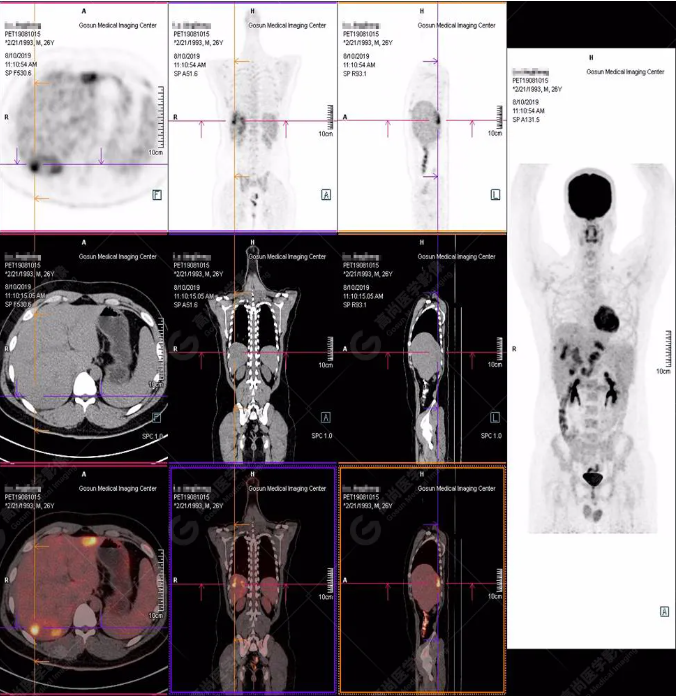

PET/CT全身圖

PET/CT診斷

嗜酸性粒細(xì)胞增多癥肝浸潤

B超及CT檢查發(fā)現(xiàn):肝臟多發(fā)低密度占位。